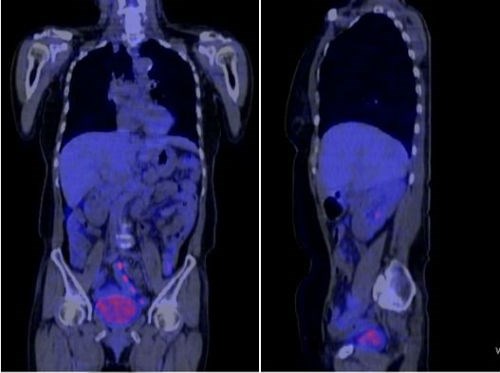

Hình ảnh phim chụp CT của bà Hà đã không còn dấu vết của ung thư.

Bà Hà được bác sĩ tiến hành điều trị hóa trị. Sau 2 chu kỳ điều trị, sức khỏe bà Hà tiến triển tốt, không sụt cân, không còn buồn nôn. Với những bệnh nhân như bà Hà, GS Khoa cho rằng đã được xác định là thành công. Các chẩn đoán dựa trên hình ảnh đều không thấy có tổn thương vùng thận, xương chậu.